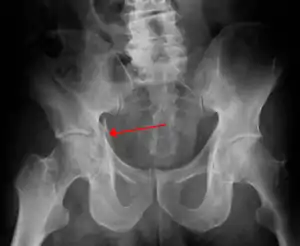

| Acetabular fracture as seen on plain X-ray |

Transverse fracture showing upper iliac fragment, lower ischial and pubic fragment

Transverse fracture fixed with screws and plate